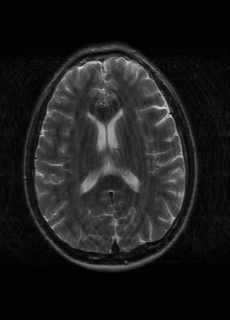

λT1=6.63subscript𝜆subscript𝑇16.63\lambda_{T_{1}}=6.63 Refer to caption (a) 34.38/0.9371 Refer to caption (b) 42.42/0.9883 Refer to caption (c) 44.60/0.9920 Refer to caption (d) 45.50/0.9940 Refer to caption (e) PSNR/SSIM

λT2=2.11subscript𝜆subscript𝑇22.11\lambda_{T_{2}}=2.11 Refer to caption (f) 29.74/0.8903 Refer to caption (g) 36.25/0.9734 Refer to caption (h) 36.42/0.9752 Refer to caption (i) 37.70/0.9832 Refer to caption (j) PSNR/SSIM

λflair=8.00subscript𝜆𝑓𝑙𝑎𝑖𝑟8.00\lambda_{flair}=8.00 Refer to caption (k) 39.89/0.9311 Refer to caption (l) 43.94/0.9864 Refer to caption (m) 44.74/0.9883 Refer to caption (n) 45.49/0.9894 Refer to caption (o) PSNR/SSIM

Figure 3: Visual comparison of different methods, with PSNR (dB) and SSIM values listed under the images. After recovery, the images are shaper with more visible details.